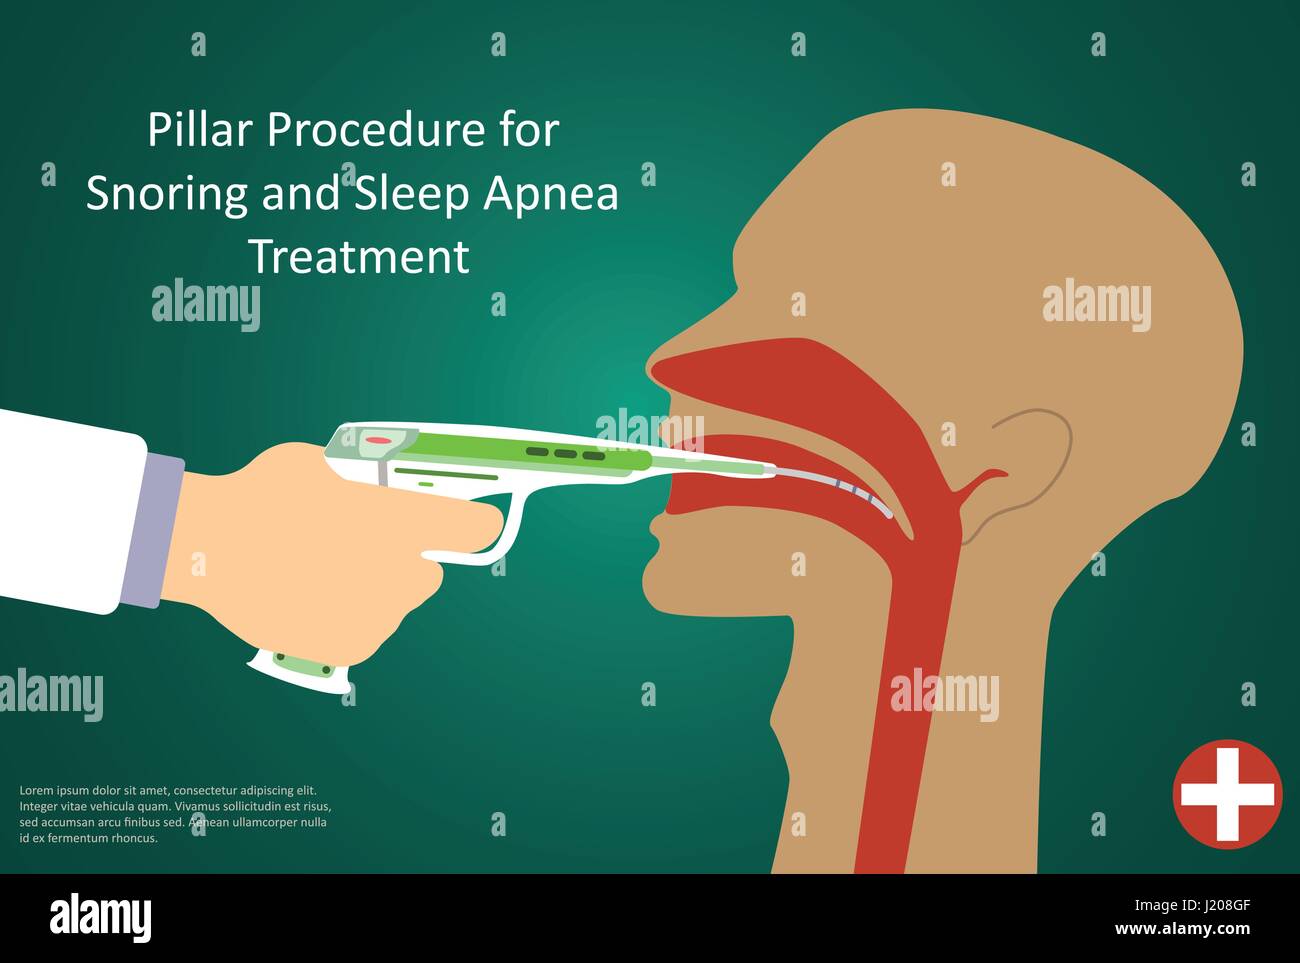

Vector illustration of procedures for sleep apnea pillar operation. Stock Vectorhttps://www.alamy.com/image-license-details/?v=1https://www.alamy.com/stock-photo-vector-illustration-of-procedures-for-sleep-apnea-pillar-operation-138918991.html

Vector illustration of procedures for sleep apnea pillar operation. Stock Vectorhttps://www.alamy.com/image-license-details/?v=1https://www.alamy.com/stock-photo-vector-illustration-of-procedures-for-sleep-apnea-pillar-operation-138918991.htmlRFJ208GF–Vector illustration of procedures for sleep apnea pillar operation.